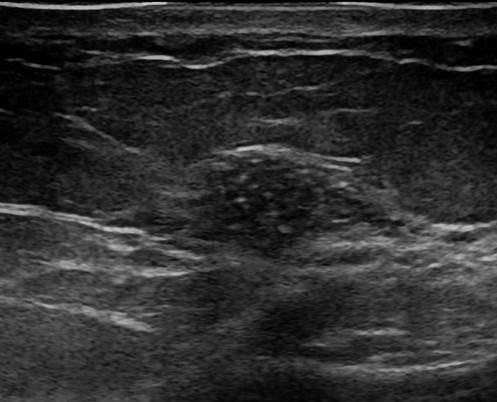

Ung thư vú

» Thông tin: Nữ giới – 42 tuổi.

» Lâm sàng: Kiểm tra sức khỏe.